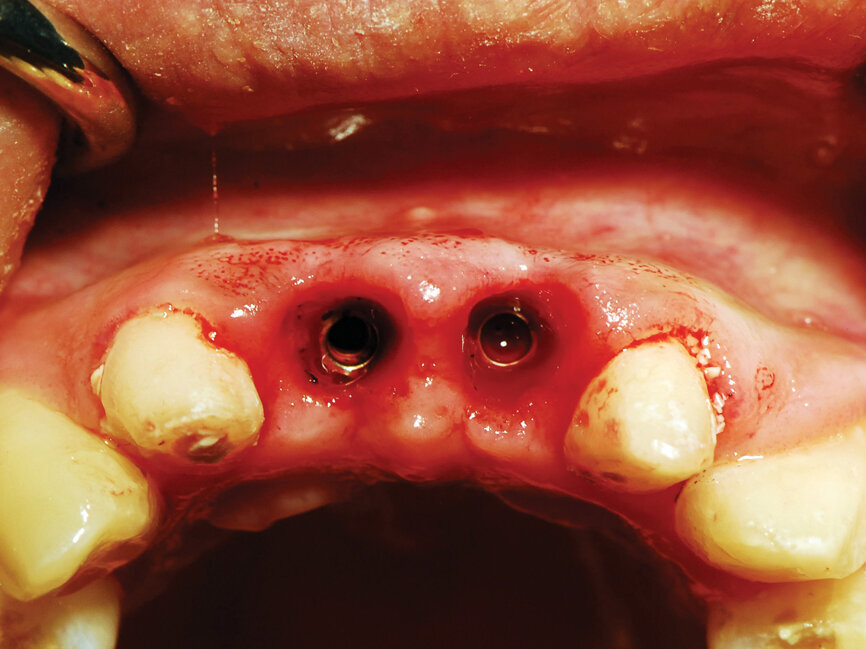

Fig. 9: Uncovery of the implants and healing screws exposed. (Photo provided by Dr. Gregori M. Kurtzman)

The process cuts the desired soft tissue and coagulates any bleeding from the cut edges. This was then repeated on the second implant (Fig. 9). Open tray implant impression abutments were placed into the implants and seating verified radiographically. An impression of the maxillary arch was taken utilizing Aquasil heavy body VPS (Dentsply Sirona, Milford, Del.) in a Mira Advanced Implant tray (Hager Worldwide, Hickory, N.C.) and Aquasil Ultra syringed around the preparations and implant abutment heads.